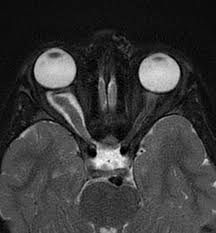

An optic nerve glioma is a type of brain tumor. There are multiple kinds of brain tumors. Typically, each type of tumor is named after the kinds of cells it affects. Most optic nerve gliomas are considered low-grade and don’t grow as quickly as other types of brain tumors. They are found in the optic chiasm, where the left and right optic nerves cross. They are also referred to as optic glioma or juvenile pilocytic astrocytoma.